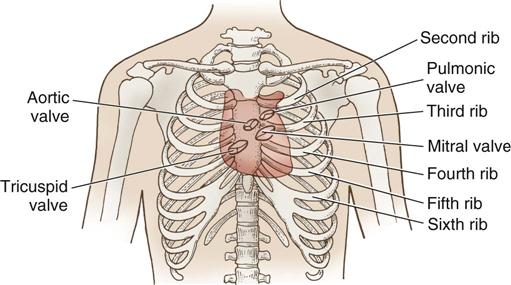

The heart (Figure 25-1) is a four-chamber muscular pump that propels blood into the systemic and pulmonary circulatory systems. It sits within a pericardial sac within the mediastinum, which lies between the lungs, posterior to the sternum, and anterior to the vertebrae, esophagus, and descending portion of the aorta. The location of the diaphragm is below the heart (Figure 25-2). The heart bears attachments at the aorta, pulmonary artery, superior and inferior venae cavae, and the pulmonary veins; the ventricles are relatively mobile, enabling the surgeon to rotate the walls of the ventricles and the apex of the left ventricle in order to assess (and graft) coronary arteries to the lateral and posterior aspects of the myocardium.

During myocardial contraction and relaxation, spiral fibers of the heart contract and relax (Figure 25-6, A). To prevent regurgitation of blood, the four cardiac valves (see Figure 25-6, B and C, and Figure 25-7) open and close to maintain unidirectional blood flow. The AV valves are between the atria and the ventricles. The right AV valve is called the tricuspid valve and contains three leaflets (or cusps). The left AV valve, called the mitral valve, consists of two leaflets (see Figure 25-6). Each AV valve is a complex system consisting of a fibrous annulus surrounding the valve orifice, the valve leaflets, the chordae tendineae, the atrium, and the papillary muscles, which anchor the valve to the inner ventricular wall (see Figure 25-1). The mitral valve annulus is a dynamic structure with a three-dimensional “saddle” shape, which has stimulated the design of newer prosthetic annuloplasty rings (Silbiger, 2012). When the ventricle contracts, these muscles and the chordae tendineae, connected to the valve leaflets, prevent the leaflets from everting into the atrium. All parts of the system must function for the valve to work properly. If the shape of the ventricle has been changed by dilation or hypertrophy, for example, the altered geometry of the ventricle impairs ventricular function. Conditions such as hypertension, myocardial injury, and aortic stenosis promote a pathologic remodeling of the heart that can lead not only to valvular dysfunction but also heart failure and malignant dysrhythmias (Gopaldas, 2012).

The semilunar valves are at the outlets of the LV and RV. These valves are known as the aortic and pulmonic valves, respectively. They have fewer components than the AV valves, and they open and close passively with cyclic fluctuations in blood pressure and volume that occur during systole and diastole.